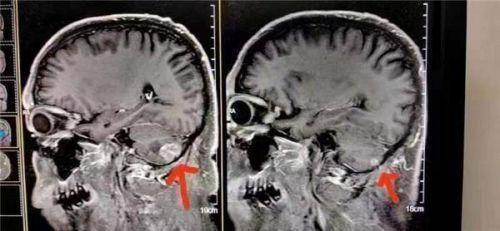

病例23:癌症小细胞脑转移

患者在北京301医院接受检查和治疗,结果显示左脑肿瘤大于右脑肿瘤。陈海林采用纯中药临床治疗,经过三个月的治疗,于2023年6月28日进行了脑磁共振平扫,共10个对比:1。与2023年3月9日的MR片相比,右小脑转移瘤复查,病变基本消失。这一结果甚至被301医院称为奇迹。

Case 22: Small cell lung cancer with brain metastasis

The patient underwent examination and treatment at Beijing 301 Hospital, and the results showed that the left brain tumor was larger than the right brain tumor. Chen Hailin adopted clinical treatment with pure Chinese medicine, and after three months of treatment, on June 28, 2023, the brain magnetic resonance plain scan with ten contrasts: 1. Compared with the MR film on March 9, 2023, the right cerebellar metastatic tumor reexamined and the lesion basically disappeared. This result is even claimed to be a miracle by Hospital 301.